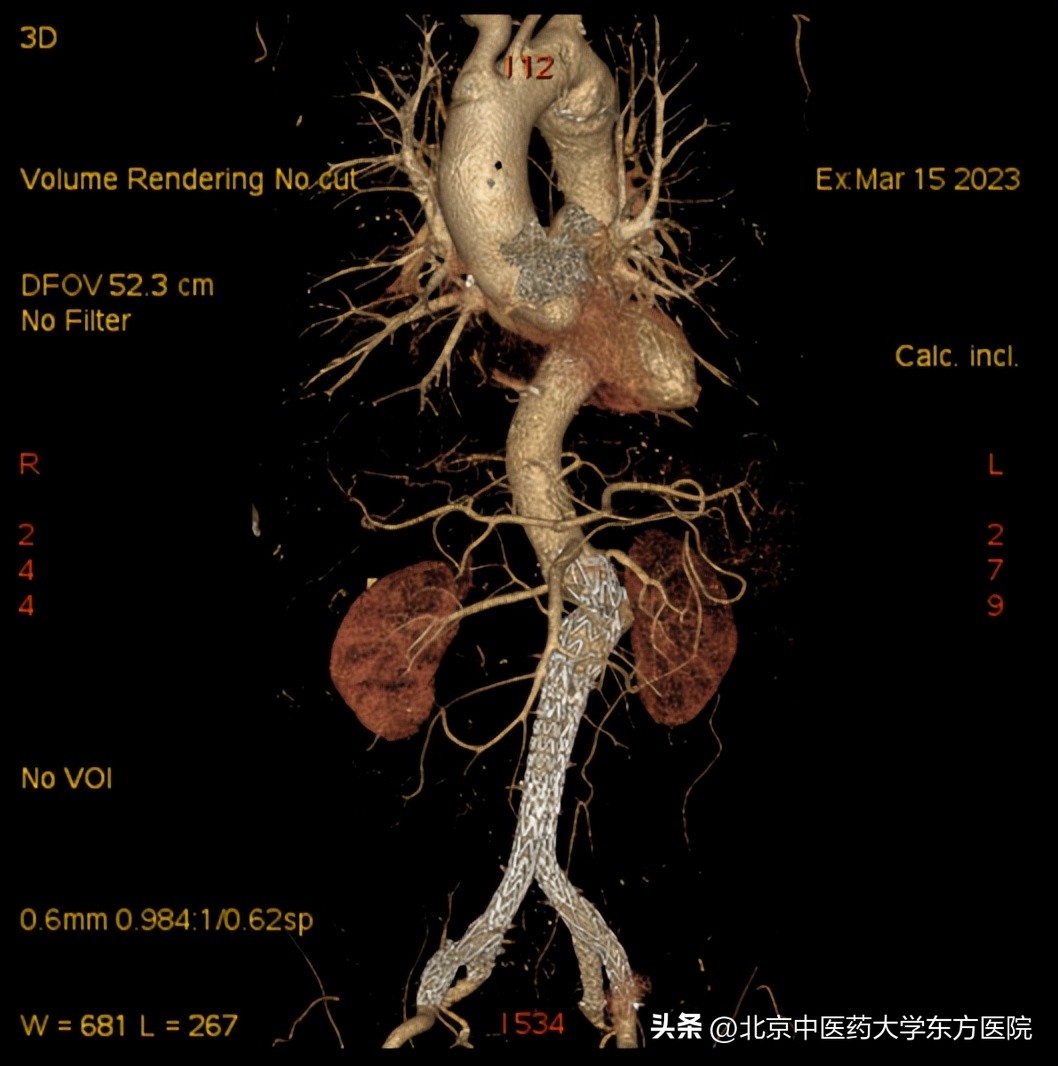

入院后外四科团队在对病例进行全面分析、充分讨论,患者年龄相对较轻,结合其盆腔供血情况,为达到更佳疗效,避免并发症的发生,故决定在“拆除腹腔定时*弹炸**”的同时,重建双侧髂内动脉的手术方式,不放弃任何一条血管,力争完美解决腹主动脉和髂动脉血管瘤体问题,并且对患者的正常功能最大程度的保留。经过术前模拟等周密准备,由科室杨宝钟主任指导,顾汉程、黄强、曹刚、李光宗医生上台,在麻醉科、导管室、放射科以及护理同仁的通力配合下,团队历时5个半小时顺利完成该手术。术后复查支架放置精准,血流通畅,血管形态完美,无各型内漏。患者无不适症状,术后第二天正常下地活动,目前已康复出院。

(术后)